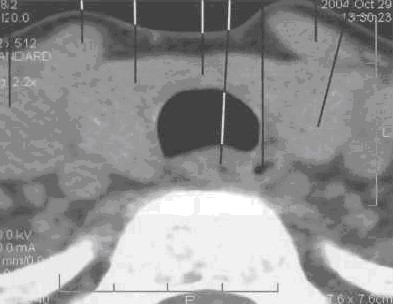

Компьютерная томография ЩЖ

КТ железы проводится от яремной вырезки до уровня Су. Толщина среза -- 8 мм, шаг -- 4--8 мм. Обычное положение неизмененной железы -- на 2 см выше верхнего края гру­дины.

Форма -- в виде двух овалов с относительно ровными контурами, хорошо отграниченными от окружающих тканей.

Поперечные размеры составляют 30x20 мм, высота -- 30--40 мм.

Структура -- однородная. Денситометрическая плотность (при содержании в паренхиме железы 0,65 мг/г йода) -- 70+10 HU.

Кпереди от железы визуализируются грудино-щитовидные и грудино-подъязычные мыш­цы, по передней поверхности которых проходят наружные яремные вены.

Латеральной поверхностью железа прилежит к внутренней яремной вене и сонной арте­рии. Слева сонная артерия лежит под веной, справа проходит ближе к телу позвонка по задне-латеральной поверхности железы.

По заднемедиальному краю щитовидной железы, кзади от трахеи располагаются паращитовидные железы, которые могут быть видны у тучных пациентов. Паращитовидные желе­зы могут визуализироваться между собственной капсулой железы и жировой клетчаткой. Число паращитовидных желез колеблется от 2--4 до 5--6. Их длина составляет 5--6 мм, толщина -- около 4 мм.

Задний край щитовидной железы отделен от тел пятого и шестого шейных позвонков длин­ной мышцей шеи. В центре среза между трахеей и серединой тел позвонков располагается пи­щевод (рис. 28)

Рис. 28. Серия КТ изображений щитовидной железы на разных уровнях щитовидного хряща в аксиальной плоскости.